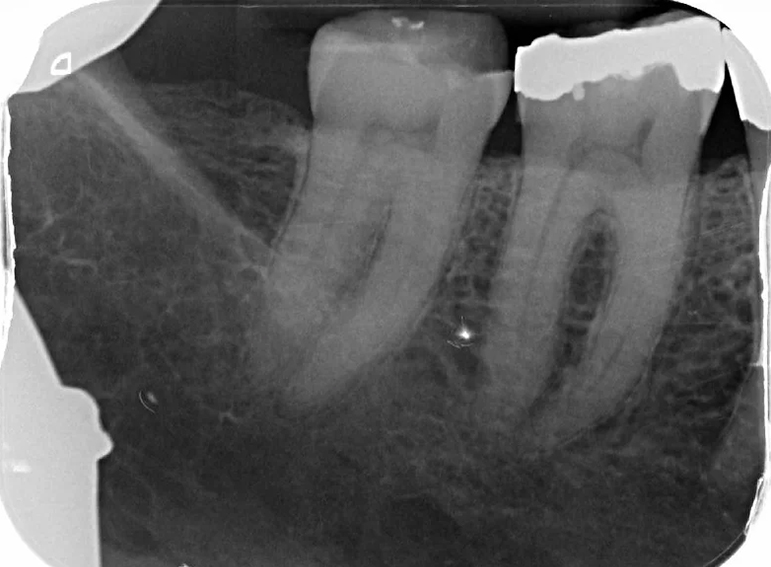

Crown lengthening surgery and adhesive onlay on a molar.